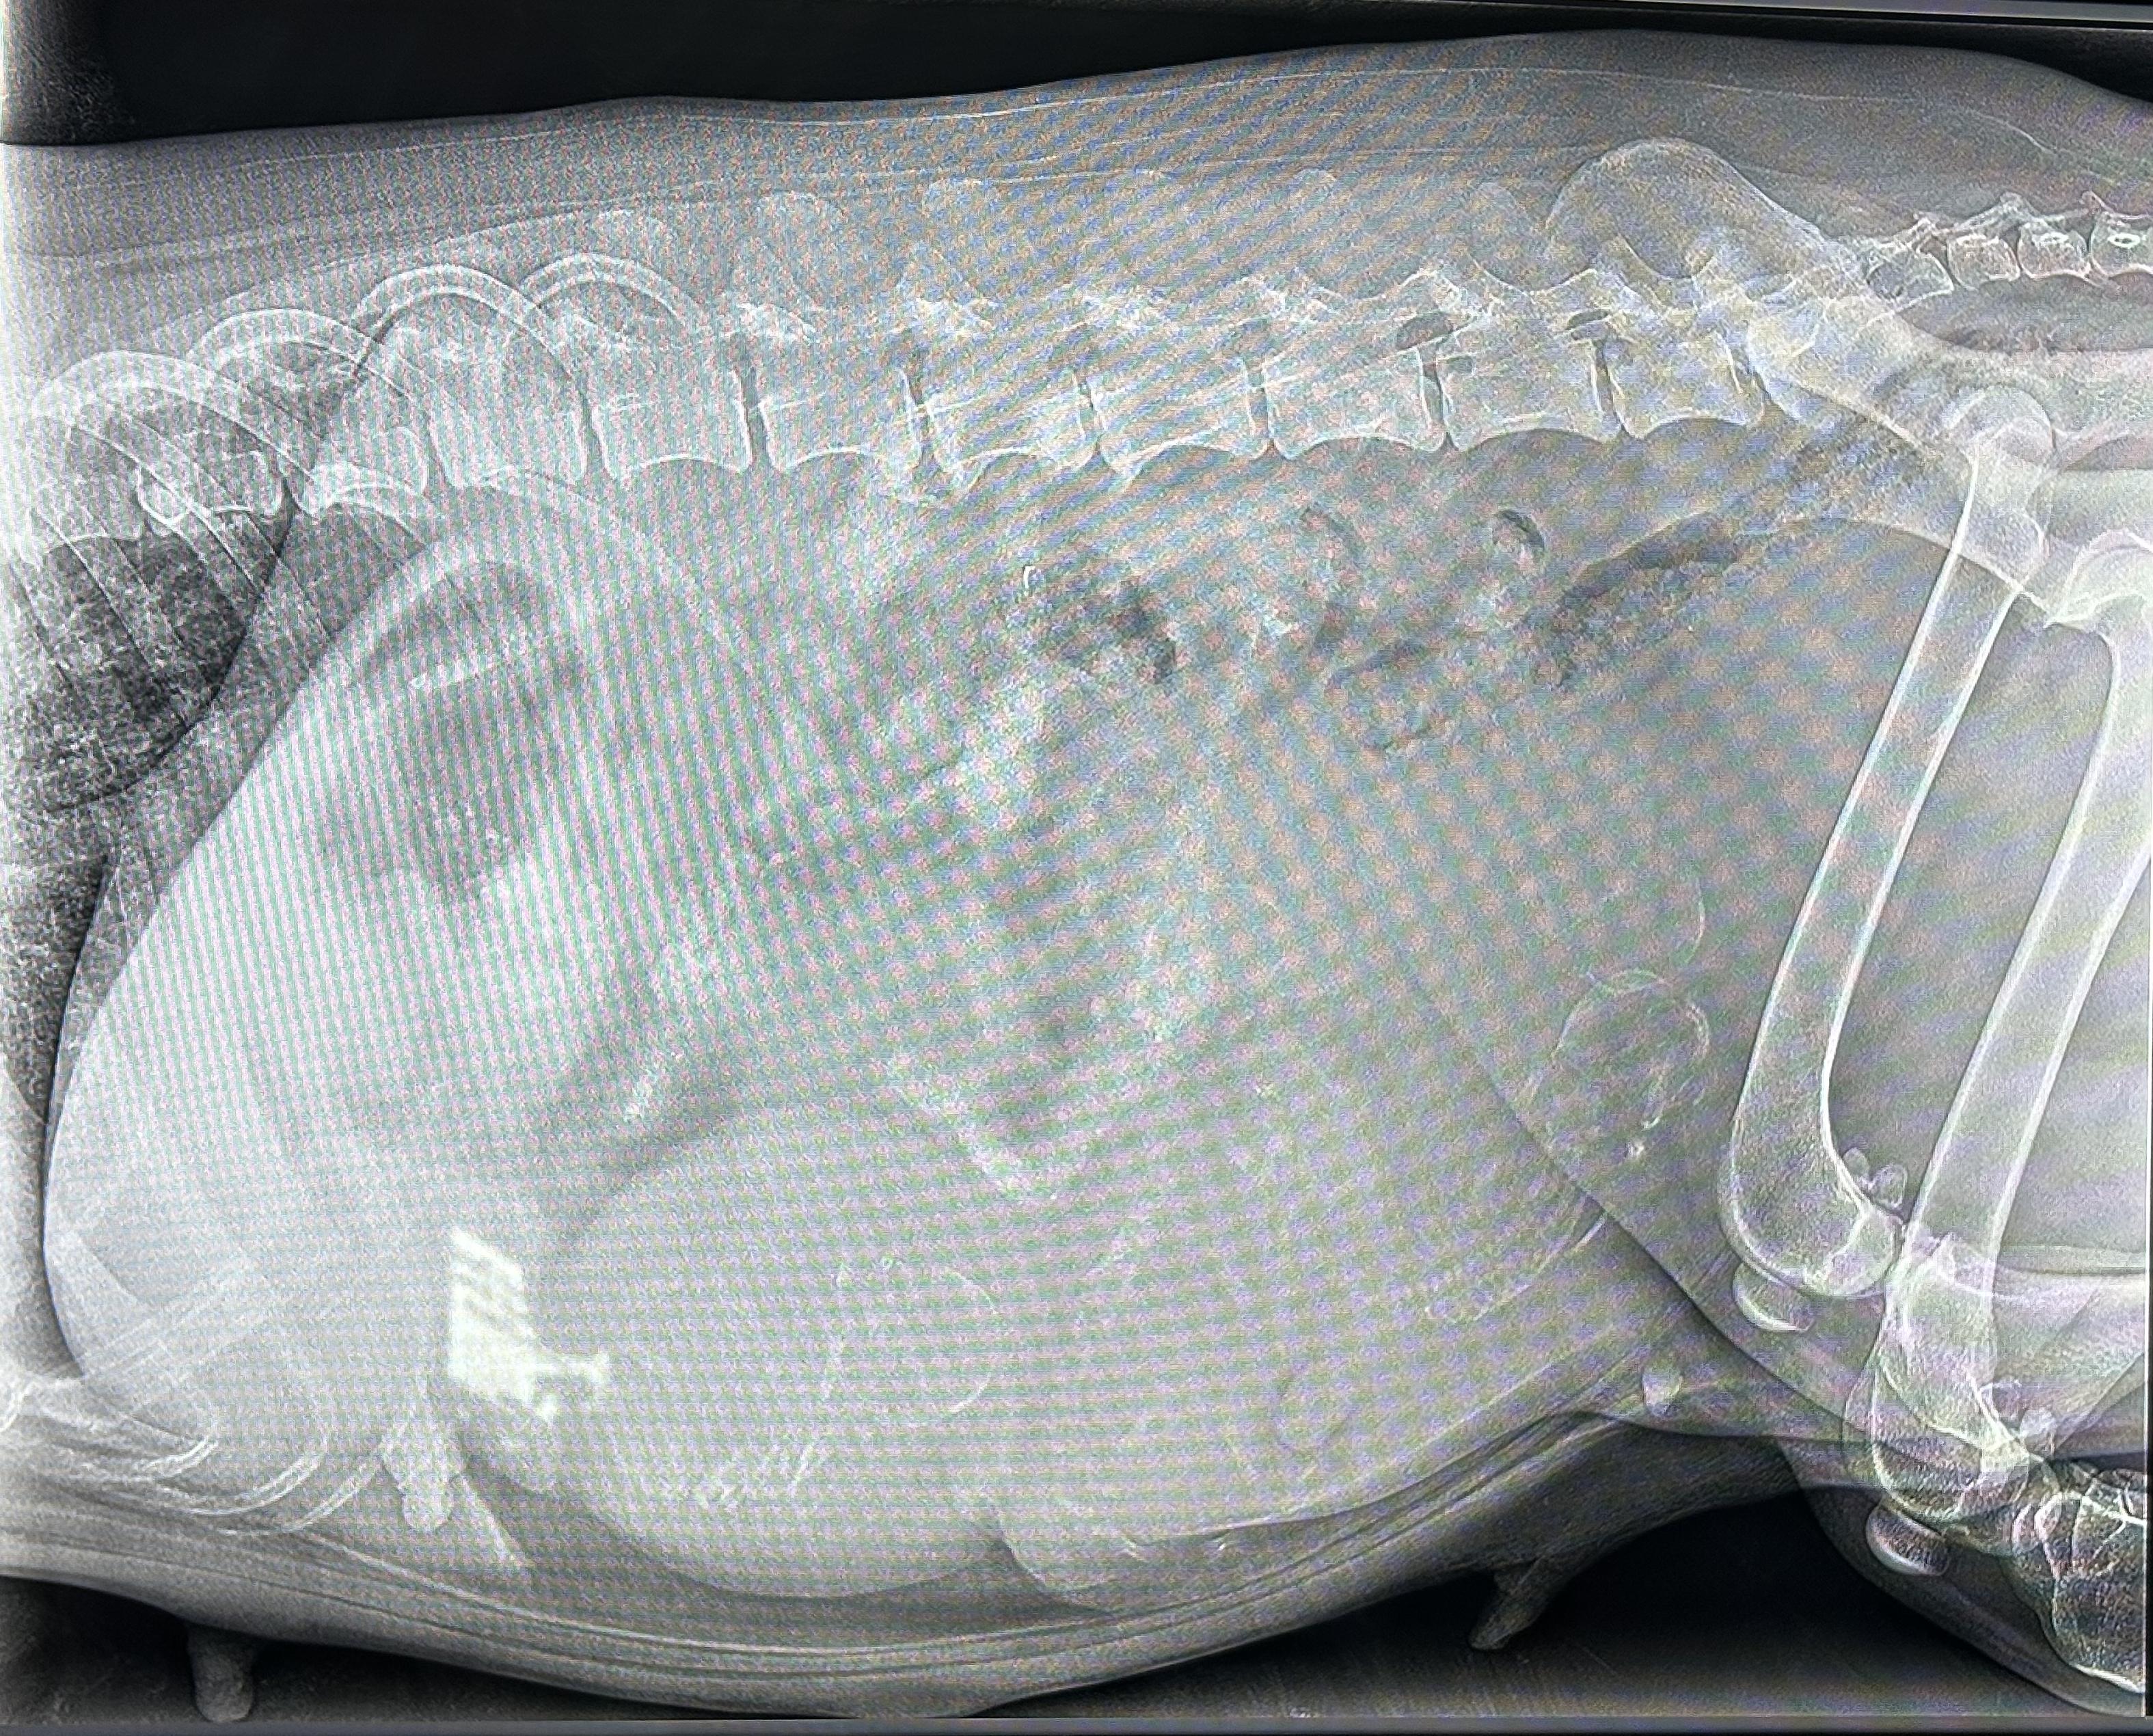

Jette hat 3 starke Jungs geboren